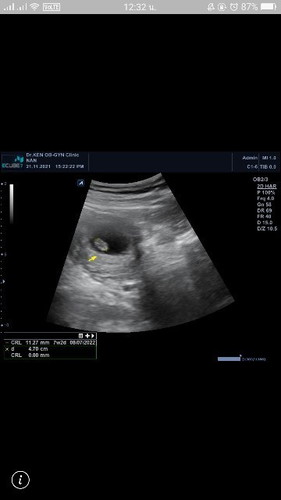

ขออนุญาติสอบถามแม่ๆค่ะ ไปอัลตราซาวล์มาเจอแต่ตัวน้องแต่ยังไมาเจอหัวใจของน้อง จะเป็นอะไรมั้ยค่ะ

บ้านนี้ท้องแรกเจอตัวน้องแต่หัวใจไม่เต้นคือน้องหยุดการเจริญเติบโตค่ะ